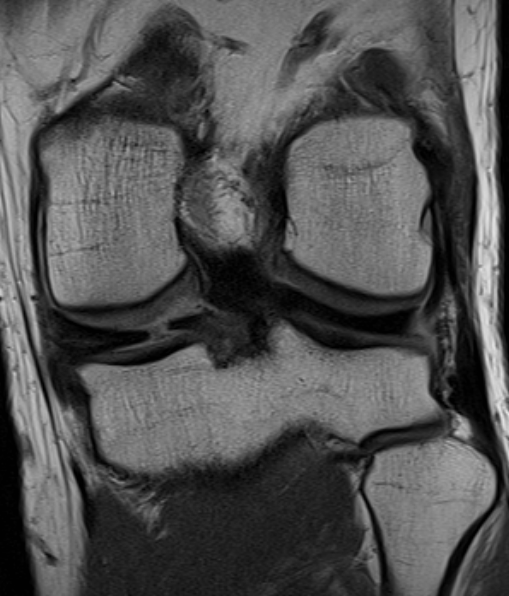

Radial tear posterior horn medial meniscus